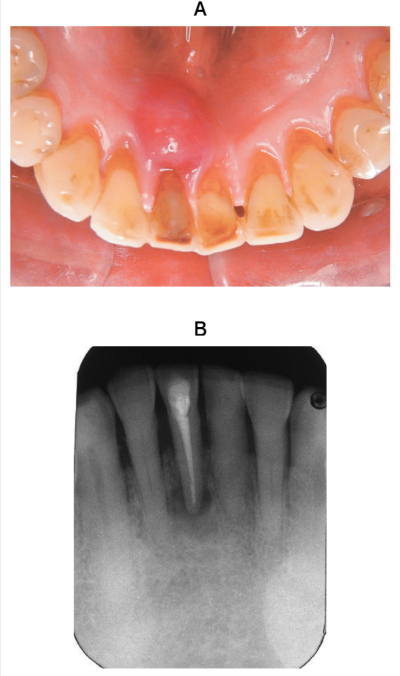

60 歳の男性。下顎右側中切歯部の歯肉腫脹を主訴として来院した。2年前に 1⏋の根管治療を受けたが、2日前に腫脹に気付いたという。現在、痛みはない。腫脹部に波動を触れる。歯周ポケット検査の結果、1⏋は全周3mm 以下であった。初診時の口腔内写真とエックス線画像を別に示す。

当日の治療で適切なのはどれか。2つ選べ。